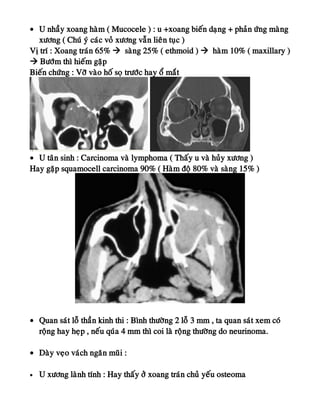

• U nhaày xoang haøm ( Mucocele ) : u +xoang bieán daïng + phaûn öùng maøng

xöông ( Chuù yù caùc voû xöông vaãn lieân tuïc )

Vò trí : Xoang traùn 65%  saøng 25% ( ethmoid )  haøm 10% ( maxillary )

 Böôùm thì hieám gaëp

Bieán chöùng : Vôõ vaøo hoá soï tröôùc hay oå maét

• U taân sinh : Carcinoma vaø lymphoma ( Thaáy u vaø huûy xöông )

Hay gaëp squamocell carcinoma 90% ( Haøm ñoä 80% vaø saøng 15% )

• Quan saùt loã thaàn kinh thi : Bình thöôøng 2 loã 3 mm , ta quan saùt xem coù

roäng hay heïp , neáu quùa 4 mm thì coi laø roäng thöôøng do neurinoma.

• Daøy veïo vaùch ngaên muõi :

• U xöông laønh tính : Hay thaáy ôû xoang traùn chuû yeáu osteoma